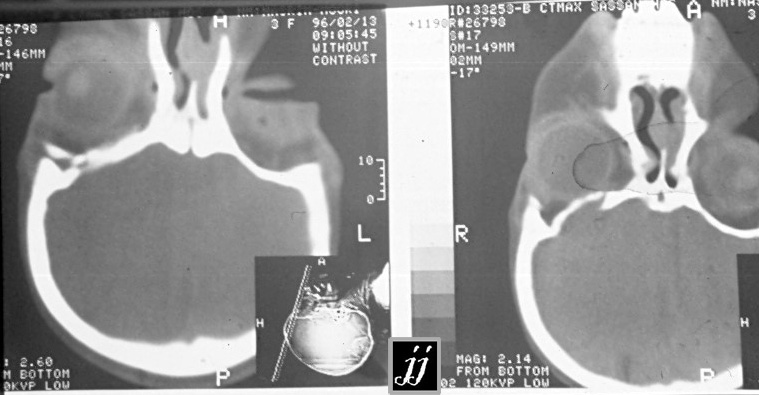

Radioogle Ent Right Orbital Roof Reconstruction